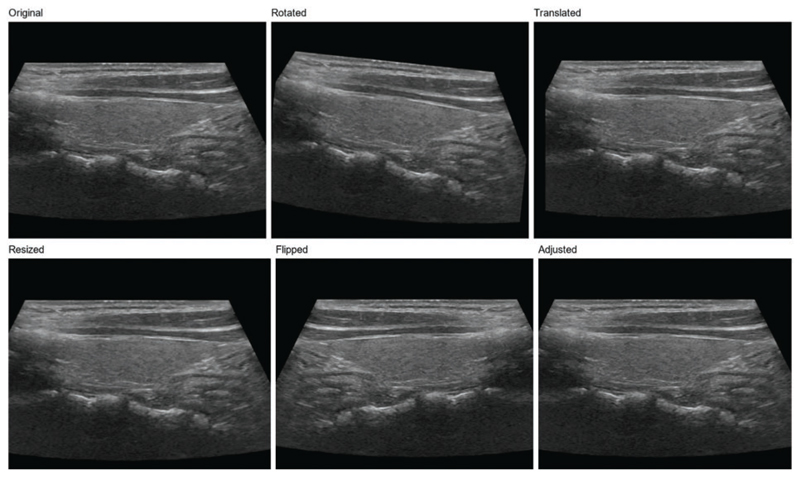

Methods: A novel method, ThyroidNet, is introduced and evaluated based on deep learning for the localization and classification of thyroid nodules. First, we propose the multitask TransUnet, which combines the TransUnet encoder and decoder with multitask learning. Second, we propose the DualLoss function, tailored to the thyroid nodule localization and classification tasks. It balances the learning of the localization and classification tasks to help improve the model's generalization ability. Third, we introduce strategies for augmenting the data. Finally, we submit a novel deep learning model, ThyroidNet, to accurately detect thyroid nodules.